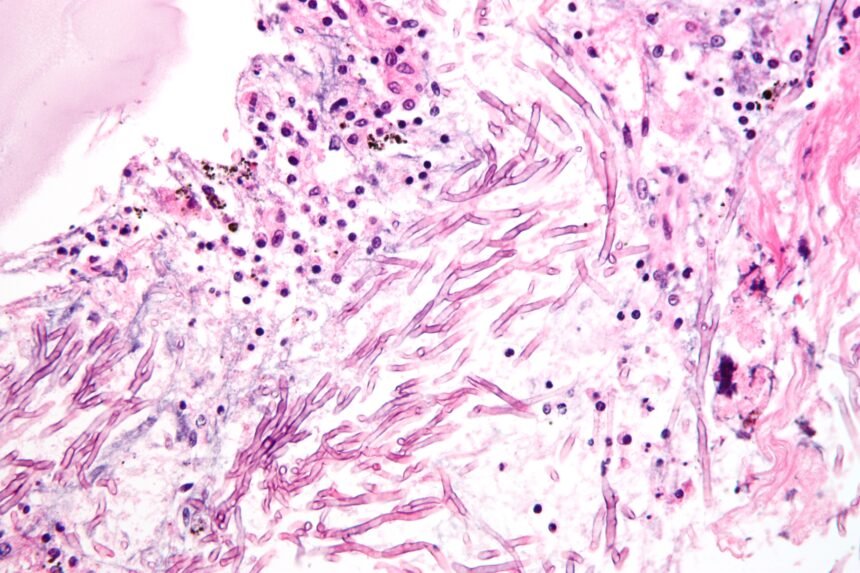

Deadly fungal infections rising present a broad spectrum of symptoms, making diagnosis challenging. Common manifestations include persistent cough, fever, shortness of breath, chest pain, fatigue, and organ-specific effects like vision or hearing impairment in cases of systemic spread. Opportunistic infections such as candidemia and invasive aspergillosis often require laboratory confirmation through blood cultures, imaging, or biopsy. Delays in diagnosis contribute significantly to high mortality rates.